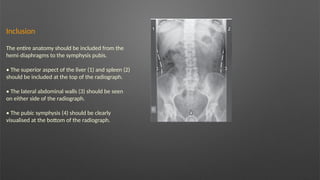

Inclusion

The entire anatomy should be included from the

hemi diaphragms to the symphysis pubis.

• The superior aspect of the liver (1) and spleen (2)

should be included at the top of the radiograph.

• The lateral abdominal walls (3) should be seen

on either side of the radiograph.

• The pubic symphysis (4) should be clearly

visualised at the bottom of the radiograph.